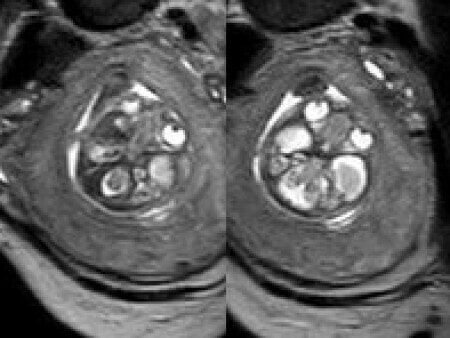

A 26-year-old primigravida with no significant past medical or family history was admitted at 18 weeks of gestation with preterm premature rupture of membranes. At 20 weeks of gestation, a detailed fetal ultrasound was performed under conditions of severe oligohydramnios, followed by fetal magnetic resonance imaging (MRI). Non-invasive prenatal testing (NIPT) for common aneuploidies was negative.

At 20 weeks, detailed ultrasound under conditions of severe oligohydramnios demonstrated absence of the typical box-shaped anechoic structure of the cavum septum pellucidum (CSP). The frontal horns of the lateral ventricles appeared narrow and pointed, giving the characteristic “bull’s horns sign.” Multiplanar and 3D reconstructions confirmed the presence of the corpus callosum, while the CSP was absent. Other midline and posterior fossa structures appeared normal. The optic chiasm was partially visualized, although assessment was limited by technical conditions. Fetal magnetic resonance imaging (MRI) was subsequently performed and confirmed isolated agenesis of the CSP with preserved corpus callosum and posterior fossa structures. The optic chiasm and pituitary stalk are visible in the sellar region, but the pituitary gland itself is not clearly identified in the sella turcica as it is a very small structure. No additional central nervous system anomalies were detected.